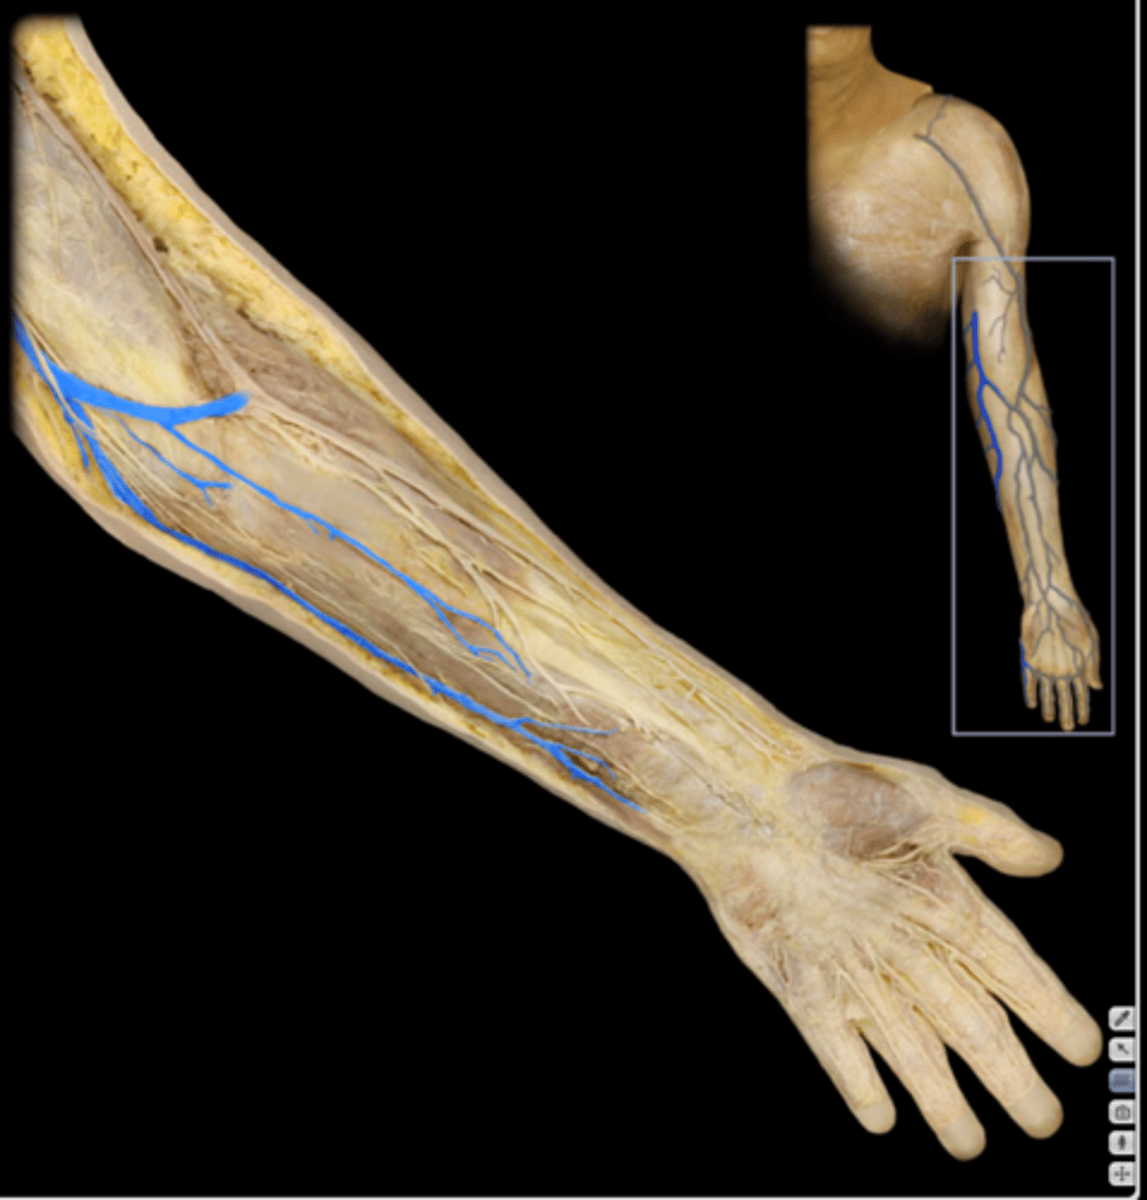

Basilic v.

A vessel of the forearm sometimes used for venipuncture

Cephalic v.

pertaining to the head

Median cubital v.

The vein most commonly accessed in the adult arm for venipuncture